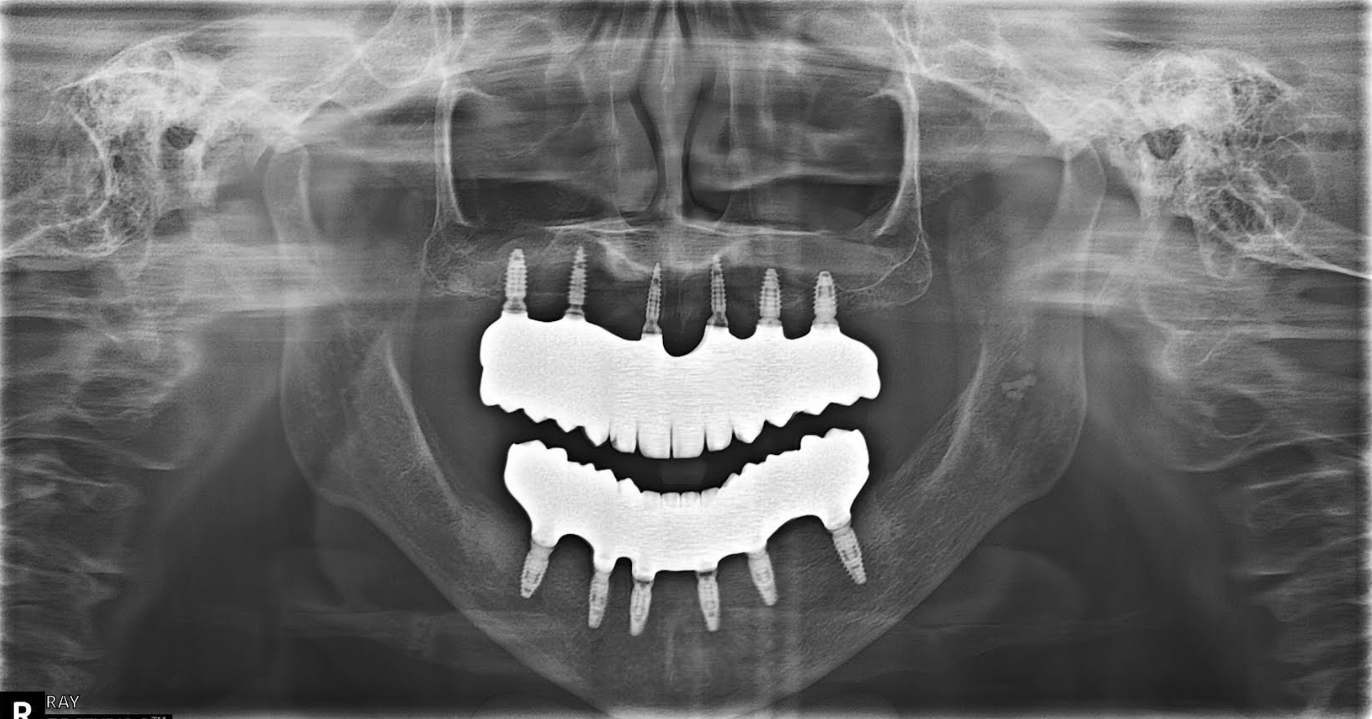

All on 6 for both arches Implants (#3,4,6,11,13,14,18,21,22,27,28,31)

The patient had her implants placed 20 years ago. Four implants, particularly in the maxilla, were not positioned ideally for me to utilize and restore, while the four implants in the mandible were outdated and no longer functional. The patient's primary concern is to restore both function and aesthetics.